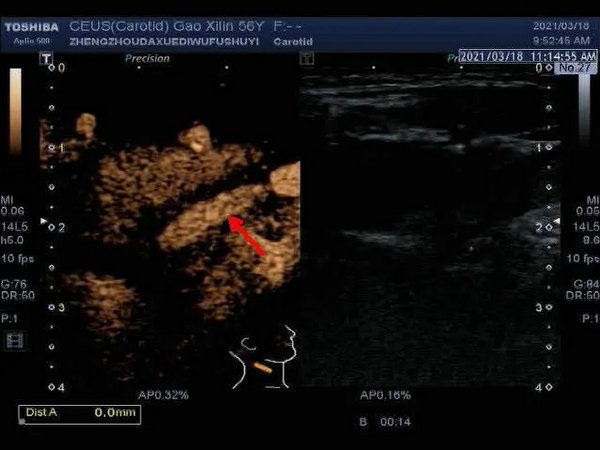

▲ 超声造影显示:红色箭头所指处为斑块新生血管

颈动脉斑块超声造影(CEUS)则是通过注射造影剂来显示颈动脉局部有无斑块、斑块大小、位置、回声、斑块内有无新生血管及新生血管含量、分布;颈动脉管腔局部有无狭窄及狭窄程度;颈动脉支架位置、局部有无再狭窄等。

目前,在颈部血管规范化超声检查基础上结合颈动脉斑块超声造影(CEUS)对血管的狭窄及斑块易损性进行综合评估,预测心脑血管事件的风险,为临床早期干预提供更为可靠的影像学信息。临床上对于有症状性颈动脉狭窄,且无创检查颈动脉狭窄度≥ 70%或血管造影发现狭窄超过50%可以行颈动脉内膜剥脱术(CEA)手术治疗。狭窄小于50%的易损性斑块可以运用血管新生抑制剂及他汀类药物改善斑块稳定性,抑制斑块进展,从而减少脑卒中发生。